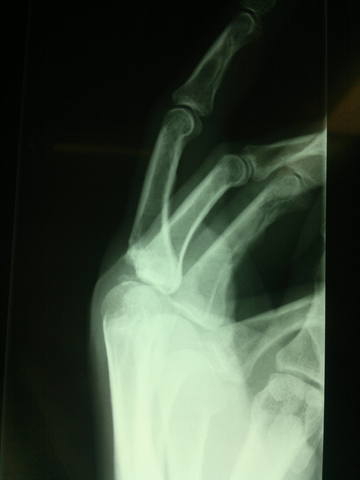

Хондросаркома головки 3 пястной кости правой кисти

Выкладываю в плане общеобразовательном, т.к. в нашей клинике мы не занимаемся лечением подобных вещей, а всего лишь выявлением.<br /><br />Около 2-х лет назад у этого 47-летнего господина появились ноющие ночные боли в области 3 пястно-фалангового сустава правой кисти, с которыми он обратился в поликлинику по месту жительства, где были сделаны первые рентгенограммы, однако пациент продолжал лечиться консервативно. Спустя 1 год симптомы заболевания не уходили и пациенту на консультации у ортопеда было предложено оперативное лечение с предварительным гистопатологическим исследованием опухолевидного образования. Исследование было проведено 2-ды и ни в одном из них не было выявлено злокачественных клеток. Операция плановая, ничего не предвещает беды, все откладывается еще на год.<br /><br />Затем пациент попадает в клинику хирургии верхней конечности, где делаются повторные рентгенограммы, на которых выявляется резорбция (остеолиз) костной ткани в области головки 3 пястной кости. Последняя увеличена в размерах, безболезненна на ощупь, кожа над ней спаяна, беспокоит незначительная боль ночью.<br /><br />

<br /><br /><br />Выполняется биопсия в 3-й раз - низкодифференцированная хондросаркома головки 3 пястной кости правой кисти. Клиническое исследование и консультация онколога - T1M0N0. Опухоль по заключению онколога не чувствительна к лучевой и низко чувствительна к химиотерапии. Рекомендована - ампутация 3-го луча. <br /><br />После чего сегодня и была выполнена эта интереснейшая операция по подробному изучению анатомии кисти и освежению в памяти навыков препарирования